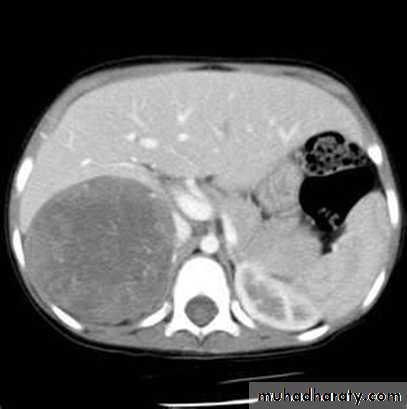

The key of the biochemical diagnosis is the assessment of potassium level and the aldosterone level.MRI or CT should be performed to distinguish unilateral from bilateral disease. Conn’s adenomas usually measure between 1 and 2 cm and are detected by CT with a sensitivity of 80–90%